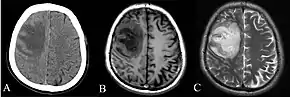

Various imaging modalities can also help with the diagnosis of melioidosis. In acute melioidosis with the spreading of the bacteria through the bloodstream, the chest X-ray shows multifocal nodular lesions. It may also show merging nodules or cavitations. For those with acute melioidosis without the spread to the bloodstream, chest x-ray most commonly shows upper lobe consolidation or cavitations.[10] In chronic melioidosis, the slowly progressing of upper lobe consolidation of the lungs resembles tuberculosis.[10] For abscesses located in other parts of the body apart from the lungs, especially in the liver and spleen, CT scan has higher sensitivity when compared with an ultrasound scan. In liver and splenic abscesses, an ultrasound scan shows "target-like" lesions while CT scan shows "honeycomb sign" (abscess with loculations separated by thin septa) in liver abscesses.[10] For melioidosis involving the brain, MRI have higher sensitivity than a CT scan in diagnosing the lesion. MRI shows ring-enhancing lesions for brain melioidosis.[10]